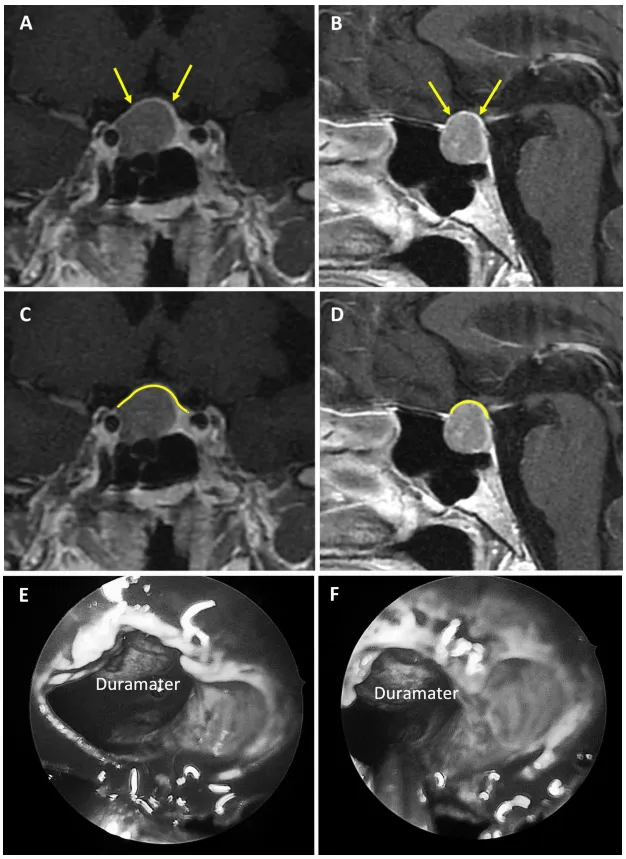

1. 强韧型鞍隔屏障案例

图2展示75岁女性无功能大腺瘤患者。a和b为术前MRI图像,黄色箭头指示厚度大于1毫米的强化屏障区;c和d为术前MRI,黄色标记线标示强韧屏障位置;e和f为术中图像,显示由垂体腺构成的屏障结构。

图3展示67岁女性无功能大腺瘤患者。a和b为术前MRI图像,黄色箭头指示厚度大于1毫米的强化屏障区;c和d为术前MRI,黄色标记线标示强韧屏障位置;e和f为术中图像,显示由硬脑膜构成的屏障结构。

图4展示47岁男性生长激素腺瘤患者。a和b为术前MRI图像,黄色箭头指示厚度大于1毫米的强化屏障区;c和d为术前MRI,黄色标记线标示强韧屏障位置;e和f为术中图像,显示由垂体腺构成的屏障结构。